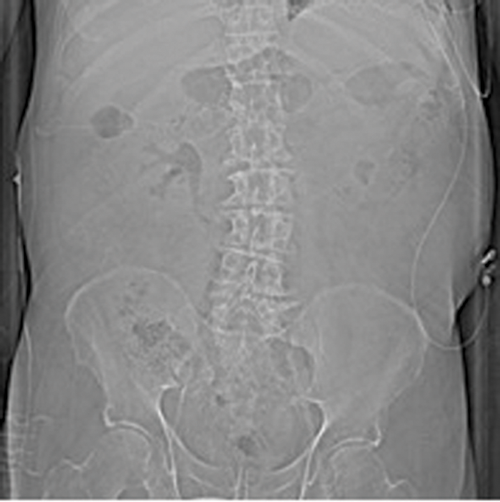

EPN should be suspected when a patient with multiple co-morbidities presents with severe sepsis and circulatory failure, combined with uncontrolled blood glucose. Other presenting symptoms include flank pain, pyrexia, vomiting, dysuria and pneumaturia. In some cases, crepitus in the flank and scrotum may be felt. Although gas may be seen on plain radiographs or ultrasound scan (USS), and ultrasound is a useful screening tool, the gold standard for imaging to determine the extent of the disease and plan intervention is a CT scan.

Figures 1: Patient A. Air in the collecting system extending into renal parenchyma.